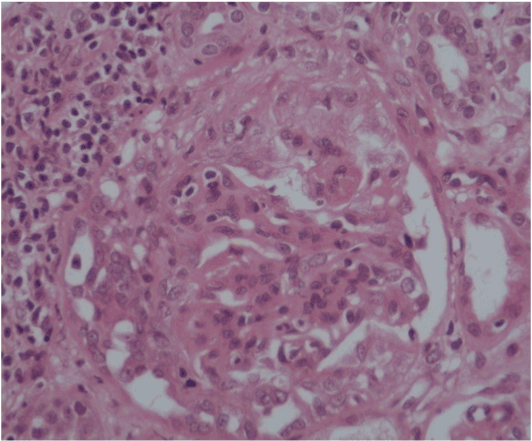

The patient was asymptomatic with normal vital signs (pulse 78/min, BP 132/78 mmHg, RR 18/min, temperature 37◦C) and in stable general condition. He had a history of controlled type 2 diabetes mellitus for 10 years (HbA1c 7%) and hypertension for 3 years, but there was no past history of renal disease or family history of kidney disease. There was no recent systemic viral or bacterial infection, no recent blood or fluid loss, and no recent exposure to nephrotoxic drugs or radiocontrast agents. Funduscopic examination revealed no diabetic or hypertensive retinopathy. Ultrasound examination showed normal size kidneys with no focal dilated collecting system and no significant post-residual urine volume. His initial urine analysis showed RBCs 3-4/hpf and albumin was +++. Serum creatinine was 4.5 mg/dl (eGFR 14 ml/min) and proteinuria 400 mg/24hour urine collection. Serum IgA level was within normal range (68-432 mg/dl). His serology reports revealed negative ANA, anti-DNA, ANCA, and anti-GBM antibody, but slightly decreased C3 and normal levels of C4. Immunoglobulins and cryogolbulins were within normal limits, HBsAg, antibodies to HCV and HIV were all negative. Repeated urine analysis showed 25 pus cells, 3+ proteinuria and many RBCs/hpf. The pus cells, and RBCs, indicated urinary tract infection, possibly due to Foley’s catheterisation. Urine culture and sensitivity revealed Proteus bacterial growth which was sensitive to imepenem. Repeated urine analysis showed no pus cells and urine culture showed no growth following treatment with a course of imepenem. His blood pressure was controlled (127/78 mmHg) with angiotensin converting enzyme inhibitor (Perindopril 5mg OD). The sudden, rapid and unexplained deterioration in renal function, and the absence of diabetic and hypertensive retinopathy, the decision for a diagnostic renal biopsy was taken. The patient was bed-bound due to fixed flexion deformities of lower limbs and deformity of left arm, and it was difficult to perform a renal biopsy in a suitable position. However, a week later and under effect of sedation, a real time renal biopsy was performed in right lateral position under ultrasound guidance. Post-procedural condition of the patient was uneventful. Light microscopy showed 32 glomeruli with prominent mesangial proliferation, fibrocellular crescent formation in 4 glomeruli, 2 glomeruli were sclerosed, and there was moderate degree of interstitial inflammation and tubular atrophy (Figure 1a and 1b). The immunofluorescent stained sections showed focal mesangial and capillary wall deposits for IgA and C3 (Figure 2).

Figure 1a.  Light microscopy: Fibro-cellular crescent formation and mesangial proliferation